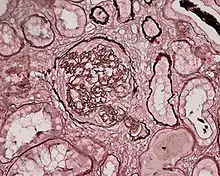

| Photomicrograph of a kidney biopsy from a person with crescentic glomerulonephritis showing prominent fibrocellular crescent formation and moderate mesangial proliferation in a glomerulus. Hematoxylin and eosin stain. | |

Rapidly progressive glomerulonephritis

Rapidly progressive glomerulonephritis, also known as crescentic GN, is characterised by a rapid, progressive deterioration in kidney function. People with rapidly progressive glomerulonephritis may present with a nephritic syndrome. In management, steroid therapy is sometimes used, although the prognosis remains poor.[9] Three main subtypes are recognised:[4]:557–558

Histopathologically, the majority of glomeruli present "crescents". Formation of crescents is initiated by passage of fibrin into the Bowman space as a result of increased permeability of glomerular basement membrane. Fibrin stimulates the proliferation of endothelial cells of Bowman capsule, and an influx of monocytes. Rapid growing and fibrosis of crescents compresses the capillary loops and decreases the Bowman space, which leads to kidney failure within weeks or months.